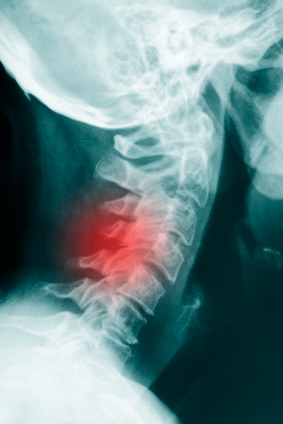

Видео рентгеноскопии является одним из видов рентгеноскопии, который использует видео для сбора и хранения изображений. Рентгеноскопия является сбор рентгеновских лучей, когда пациент совершает акт, такие как глотание. Изображения позволяет врачу наблюдать за функции организма в режиме реального времени движение. Он широко используется для изучения функции легких и диафрагмы, кости шеи и анализ глотания.

Типичные осложения:Осложнения встречаются редко. Существует несколько облучения форме рентгеновских лучей участие.